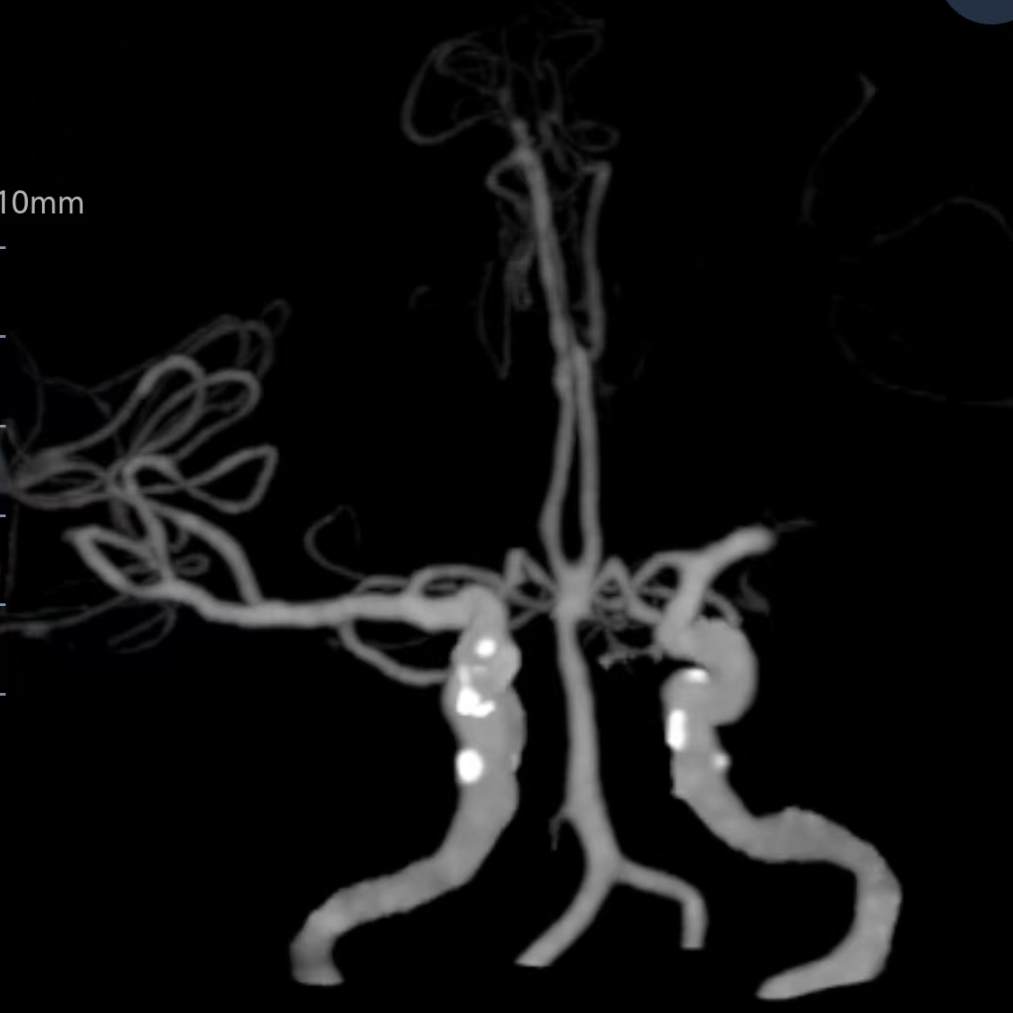

CTA提示左侧大脑中动脉闭塞

房颤栓塞致左侧大脑中动脉闭塞。